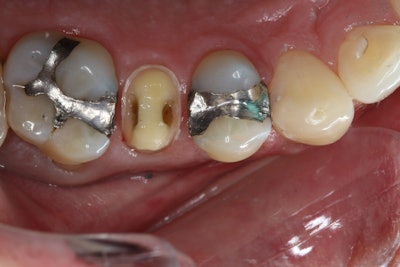

The IDS technique was then initiated using the Clearfil SE Protect system. The self-etching primer was applied for 20 seconds, gently air-dried, and followed by the application of the SE Protect bonding agent, which was light cured for 10 seconds (Figure 3).

Figure 3.

To insulate and protect the pulp in areas of deep decay, a 0.5-mm layer of Clearfil Majesty Flow flowable composite was placed and light cured for 20 seconds. Subsequently, Clearfil AP-X Composite was incrementally placed and cured in 1-mm layers in areas where tooth structure had been removed, ensuring a uniform ceramic thickness for the final restoration.